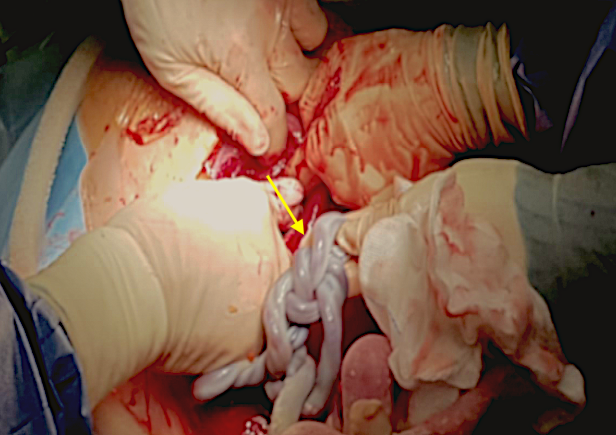

A healthy 39-year-old woman G4P3 was admitted to our high-risk pregnancy outpatient service due to a MC-DA twin pregnancy. Monochorionicity was suspected by the referring gynecologist during the dating ultrasound scan (US). The nuchal translucency US at the 12th week of gestation highlighted a “T” sign of the dividing membrane with a unique anterior placenta confirming a MC-DA twin pregnancy, as shown in Fig. 1. Soft markers for trisomy were found to be normal for both twins. The US performed during the 14th week of gestation showed the twins significantly closer to each-other standing on the same side of a free-floating thin membrane inserted on the placenta. This image raised the suspicion for a spontaneous septostomy (Fig. 2). The patient underwent amniocentesis as the combined serum screen showed an increased risk for Trisomy 21. US assisted invasive procedure did not detect the dividing membrane deposing for a PMM twin pregnancy following SS. A single sample of amniotic fluid was obtained and tested normal for fetal karyotype (46, XX). According to International Guidelines US imaging was performed every two weeks. Anomaly scan was normal and all subsequent Doppler US showed a normal twin growth and fetal wellbeing until the early third trimester [14, 15, 16]. The US performed at the 27th week of gestation showed a strict contiguity of the umbilical cords with a suspicion for cord entanglement on 3-dimensional (3D) US (Fig. 3A,B). The patient was hospitalized for close pregnancy surveillance. Fetal heart monitoring and US scan were daily performed. Steroids were administered for prevention of respiratory distress syndrome. The 29th week US scan highlighted a growth discordance ranging around 21% (symmetric growth at the 71° centile (estimated weight: 1328 gr) and at the 36° centile (estimated weight: 1043 gr) for Twin A and Twin B respectively). An episode of prolonged bradycardia was registered for Twin A. An emergency cesarean section was performed: two healthy girls were born (Twin A: weight 1360 gr, Apgar 4 and 7 at 1st and 5th minute respectively — Twin B: weight 1000 gr, Apgar 8 and 9 at 1st and 5th minute respectively). Cord entanglement was confirmed as shown in Fig. 4. The mother’s postoperative recovery was uneventful. Twins’ developmental follow-up at 12 months of age was normal.

Fig. 4.Intraoperative imaging of the cord entanglement during emergency cesarean section.